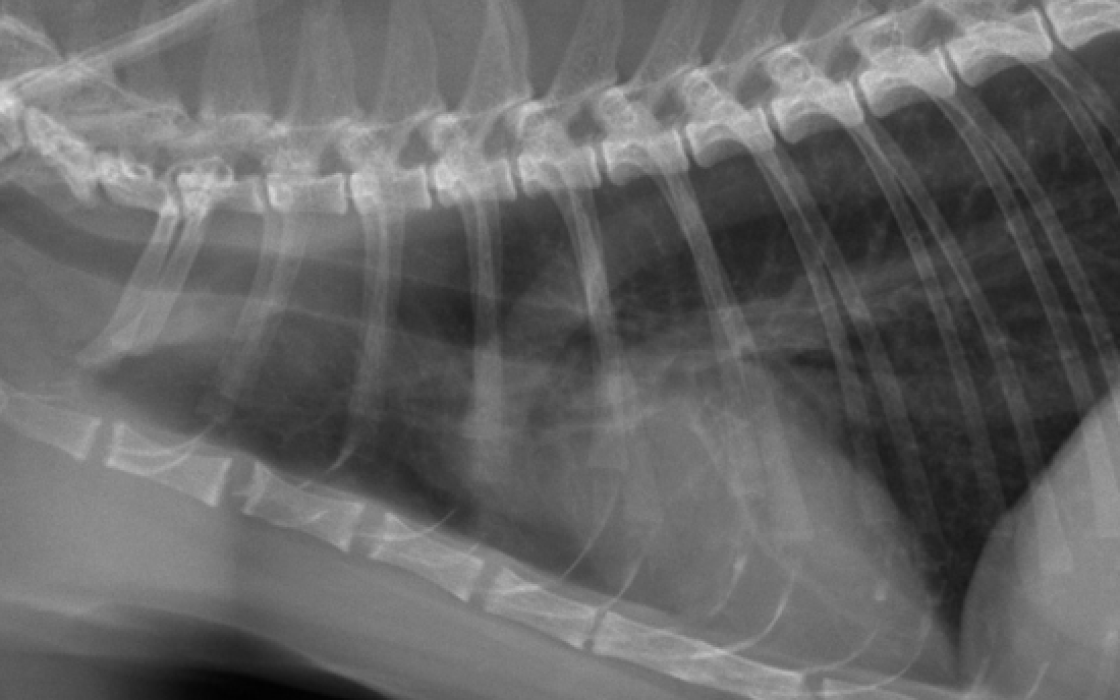

Les patterns pulmonaires à la radiographie

Les maladies pulmonaires chez le chien et le chat se traduisent généralement par une augmentation ou une diminution de l'opacité radiographique des poumons. Ces changements d’opacité donnent lieu à une catégorisation sous forme de « pattern pulmonaire ». Les patterns étant peu sensibles et peu spécifiques, identifier et localiser... Lire l'article